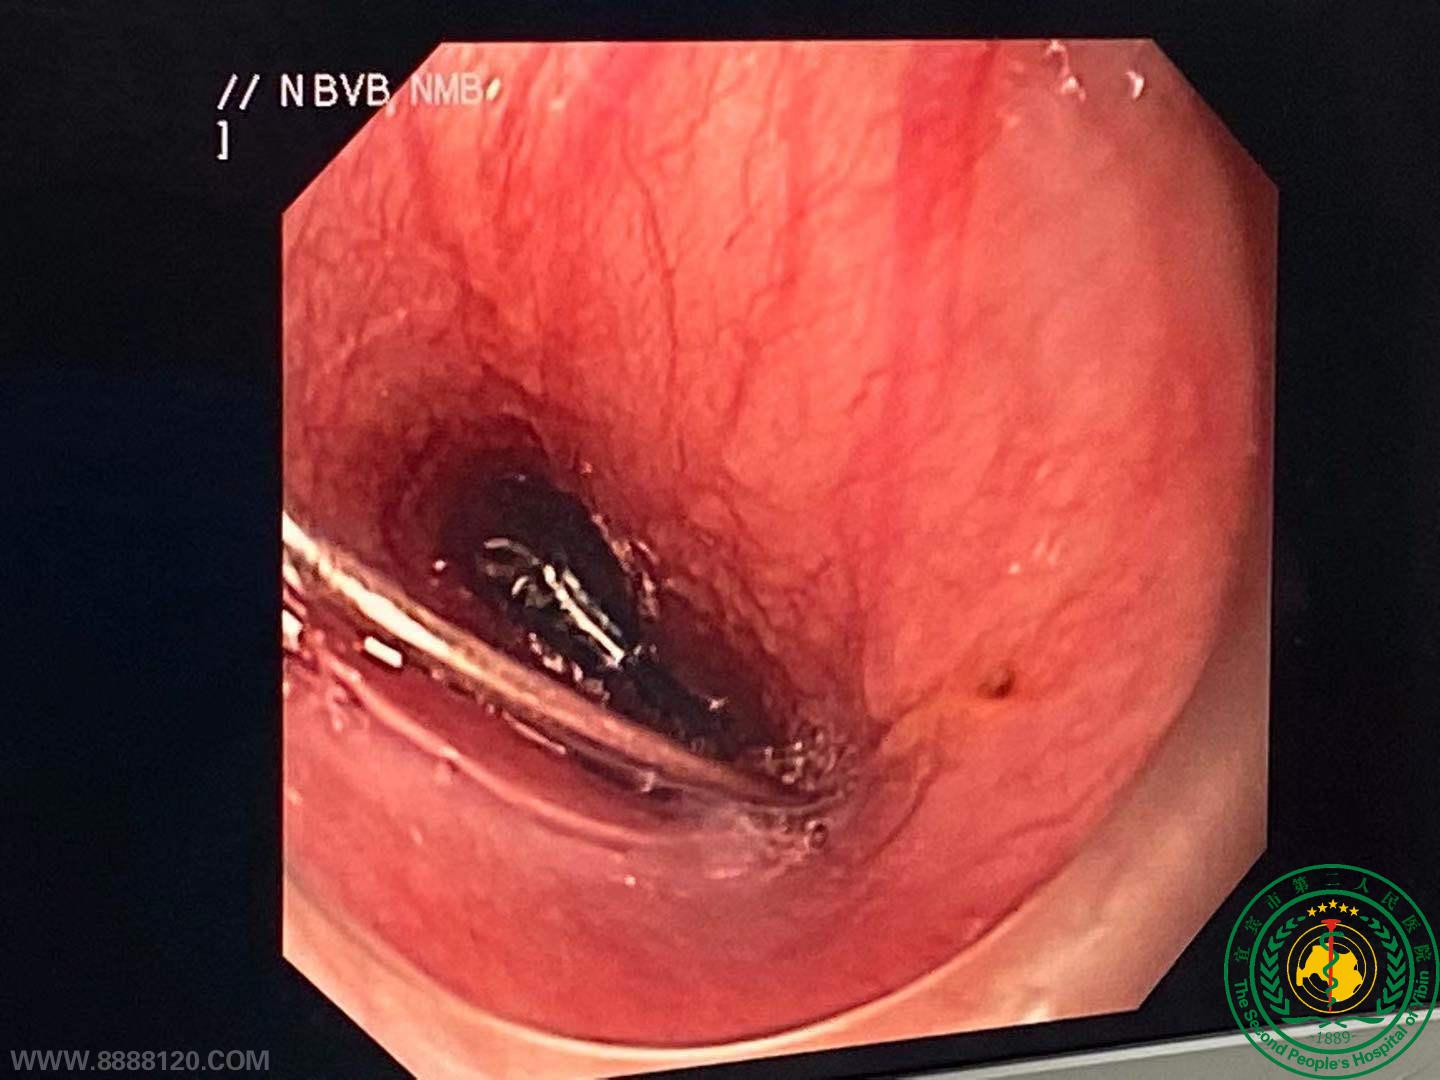

20191128日夜间,宜宾市二医院内镜中心在麻醉科及手术室的配合下,从一名11月大婴儿的食管中取出一枚打开的锁针。

11月28日下午,宜宾市翠屏区邱场镇一名只有11个月大、哭闹不止的婴儿被送到宜宾市第二人民医院妇女儿童院区急诊科就诊。家长怀疑婴儿吞了别针,但是并不确定。经小儿外科胸片检查,确定有金属异物,判断异物卡在食道内。X片提示别针打开状态,针尖向上,急诊来我院。因患儿年龄小,无法配合,常规胃镜无法进行,刘毅主任火速协调小儿外科,麻醉科,手术室等相关科室后急诊送入手术室。麻醉成功后杨丽莎老师与张强老师精准、安全将异物取出。

上消化道钡餐内镜下见异物锁针取出